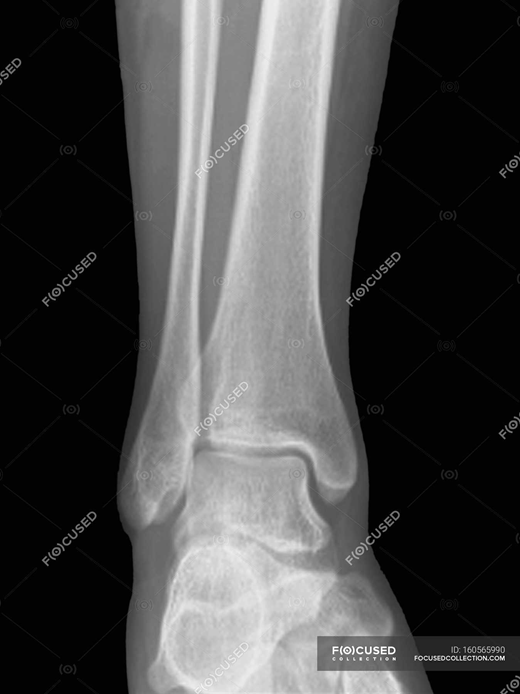

Запитання 19

РОЗПІЗНАЙТЕ КІСТКУ. ПЕРЕЛОМ ЯКОЇ ЇЇ ЧАСТИНИ ВИ БАЧИТЕ НА РЕНТГЕНОГРАМІ?

варіанти відповідей

ULNA

RADIUS

FEMUR, ШИЙКА

ПРОКСИМАЛЬНОГО ЕПІФІЗА

ДИСТАЛЬНОГО ЕПІФІЗА

ДІАФІЗА

ЛІКТЬОВОГО ВІДРОСТКА

ПРОМЕНЕВОГО ВІДРОСТКА